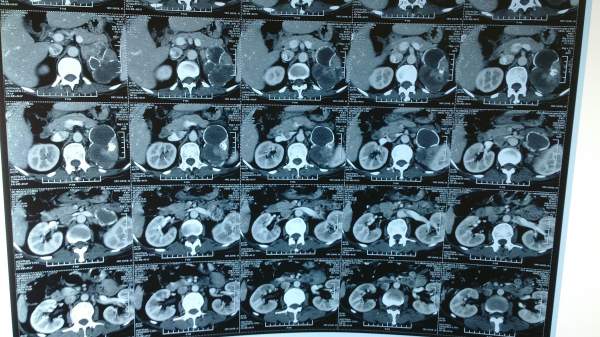

肾癌合并肾动脉血栓形成CT读片

近期在临床发现一个病例,病人因腰痛入院,查有肾动脉部分分支阻塞,肾脏占位,遂拍CT片,但是后来看不懂肾动脉的阻塞,不知在哪个部位,已经与肾脏占位的关系,现发上来,与大家分享一下,顺便求高手给予解答! IMG_20130904_112041.jpg IMG_20130904_112103.jpg |